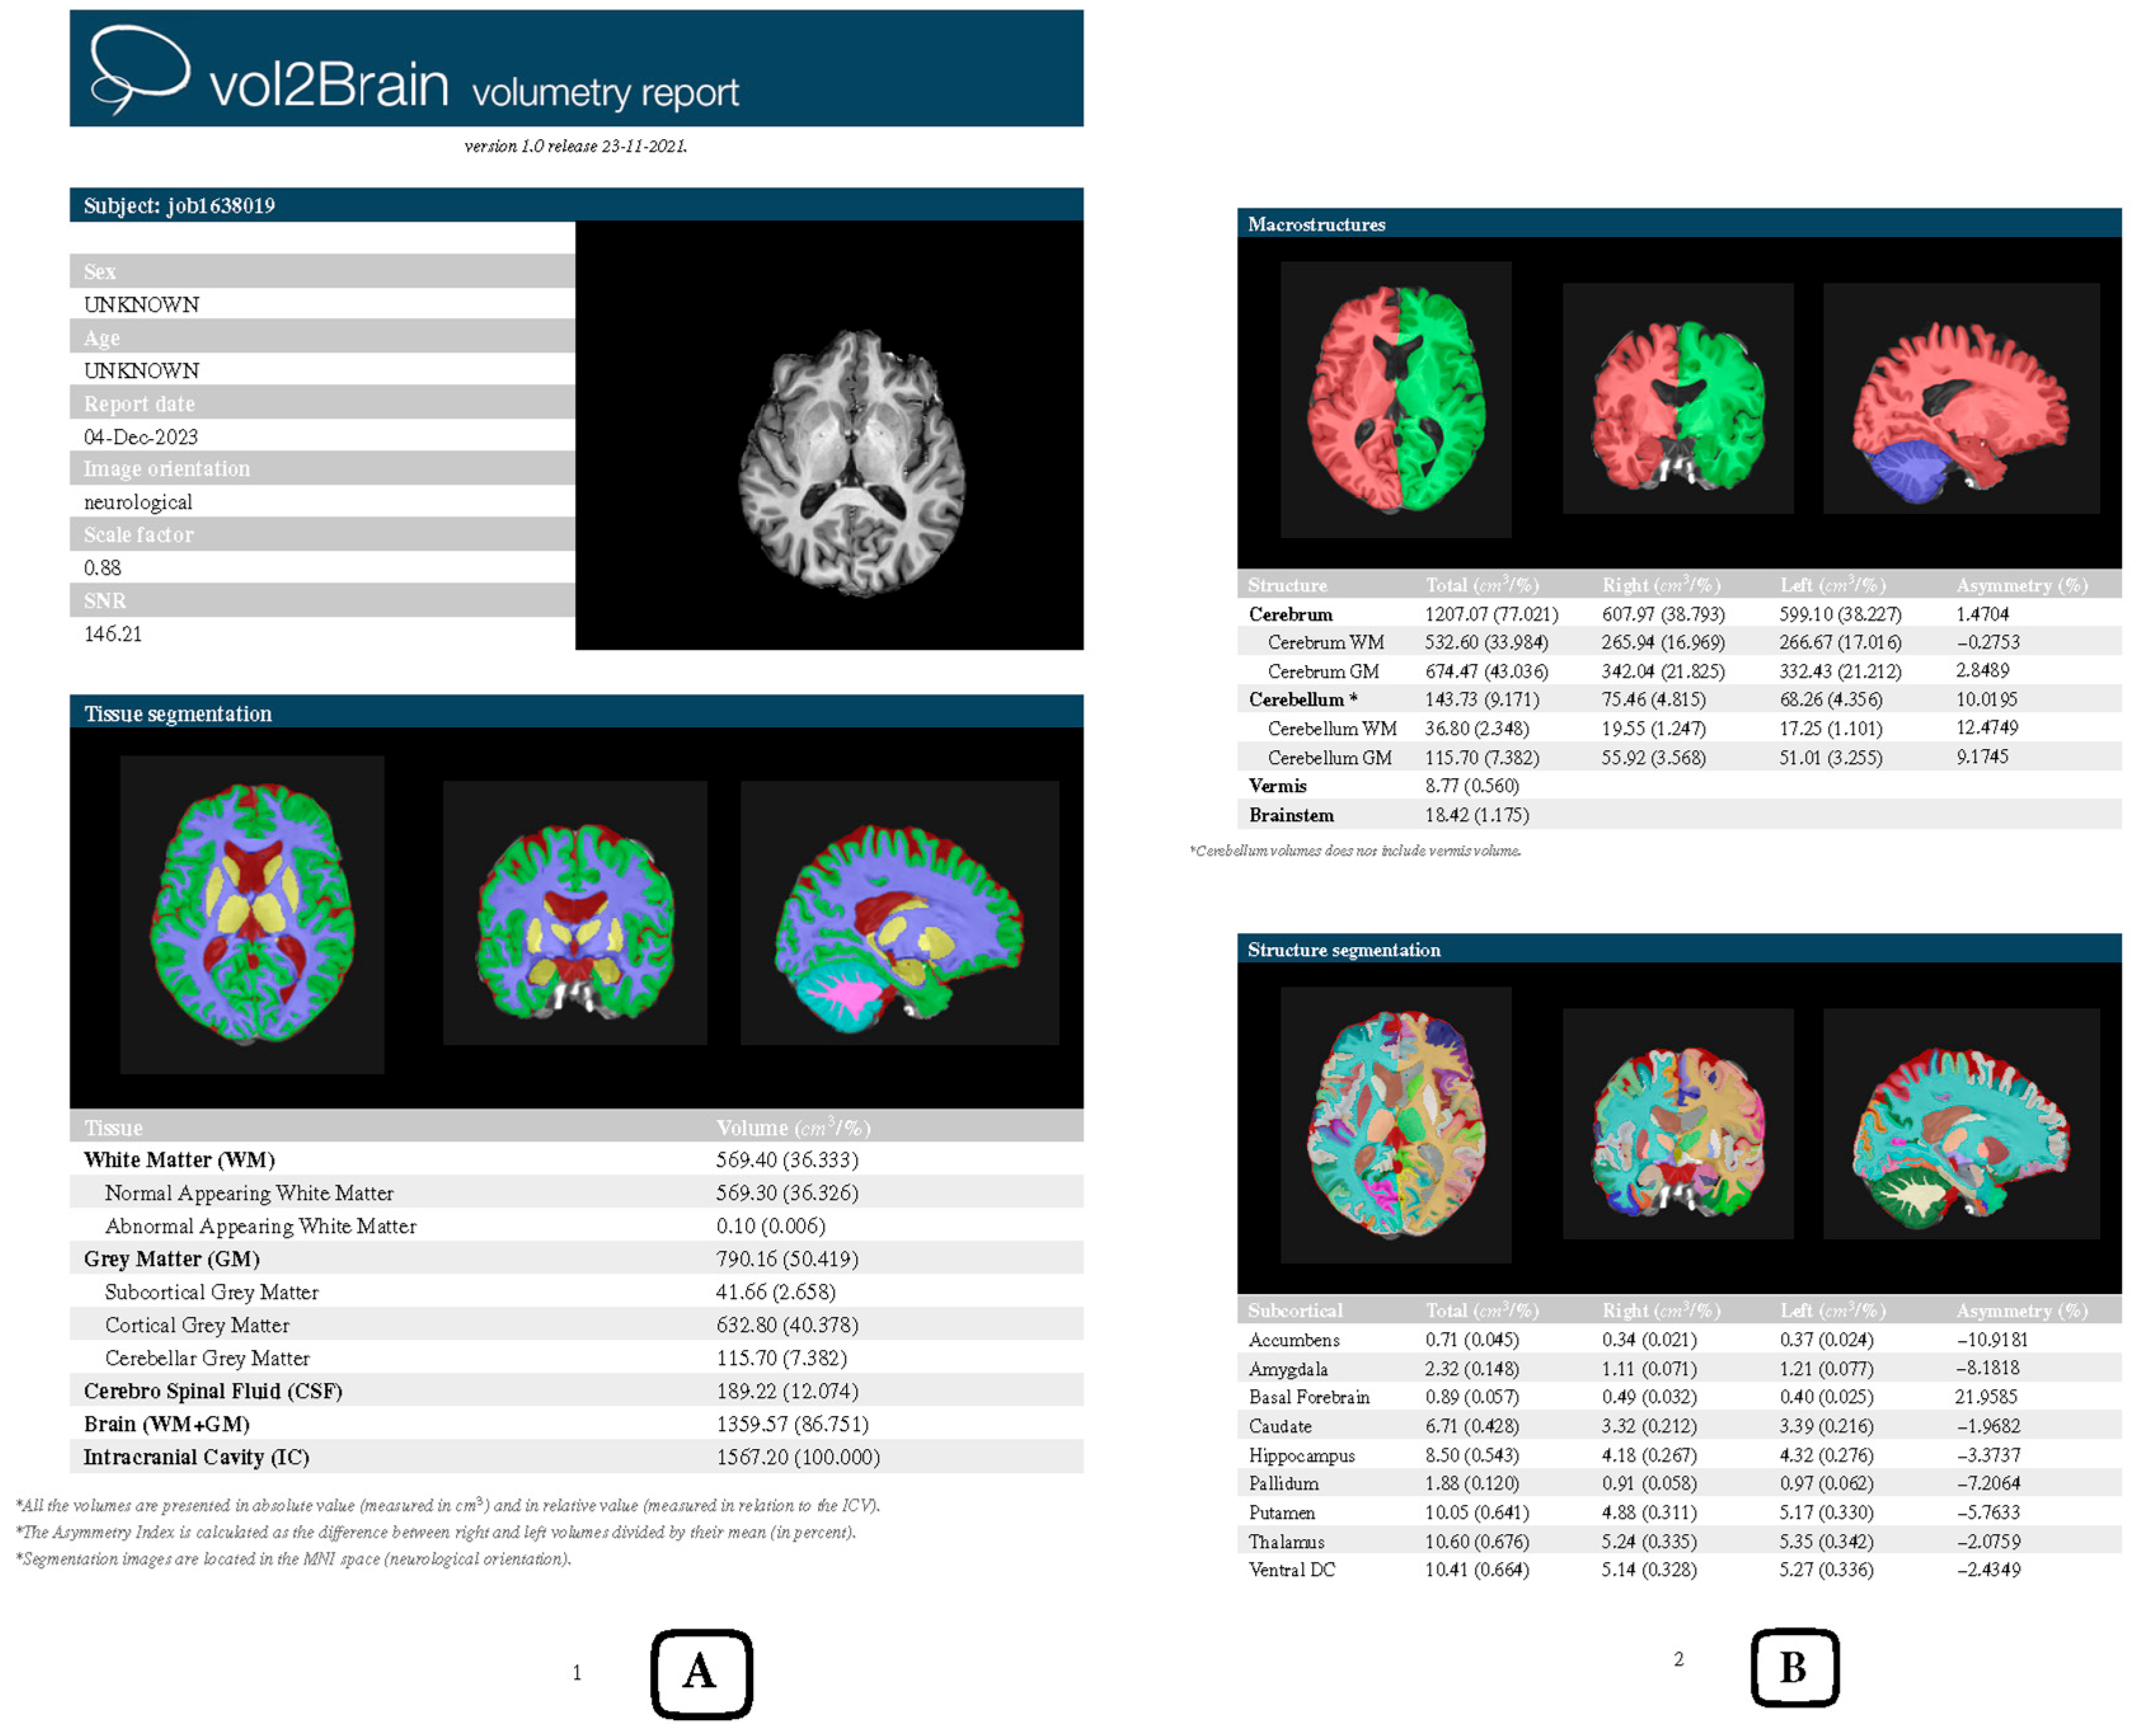

2.2. Structural MR Data Analysis